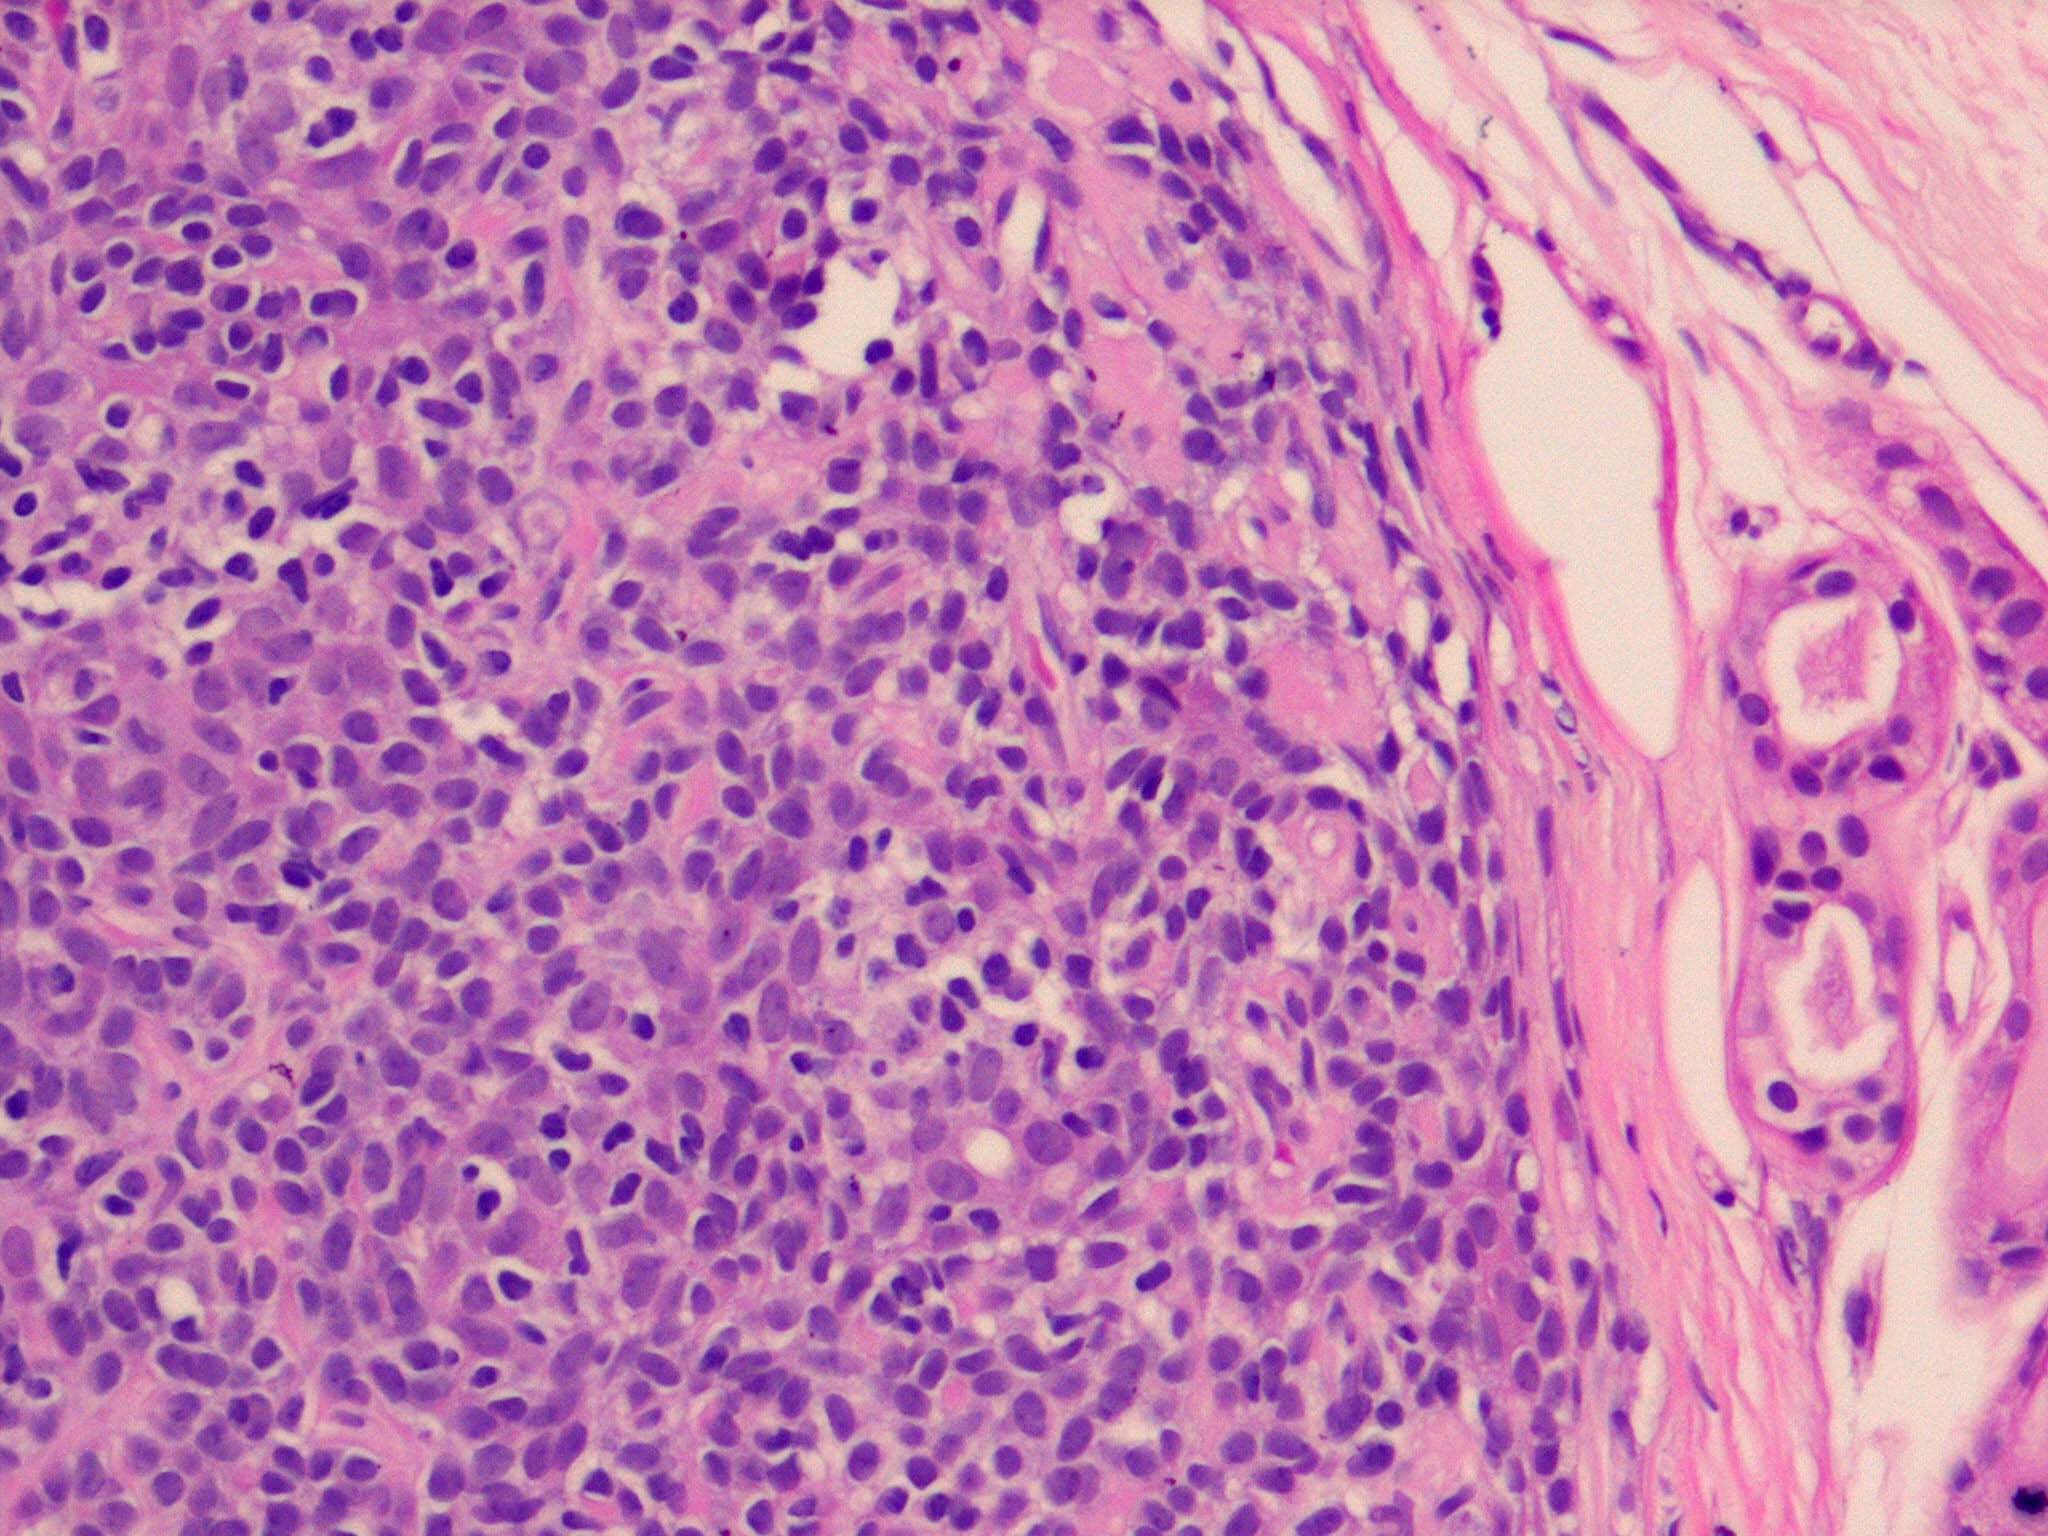

Spiradenoma=ورم غدي عرقي

OLYMPUS DIGITAL CAMERA